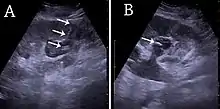

- ↑ Content initially copied from: Hansen KL, Nielsen MB, Ewertsen C (December 2015). "Ultrasonography of the Kidney: A Pictorial Review". Diagnostics. 6 (1): 2. doi:10.3390/diagnostics6010002. PMC 4808817. PMID 26838799. (CC-BY 4.0)